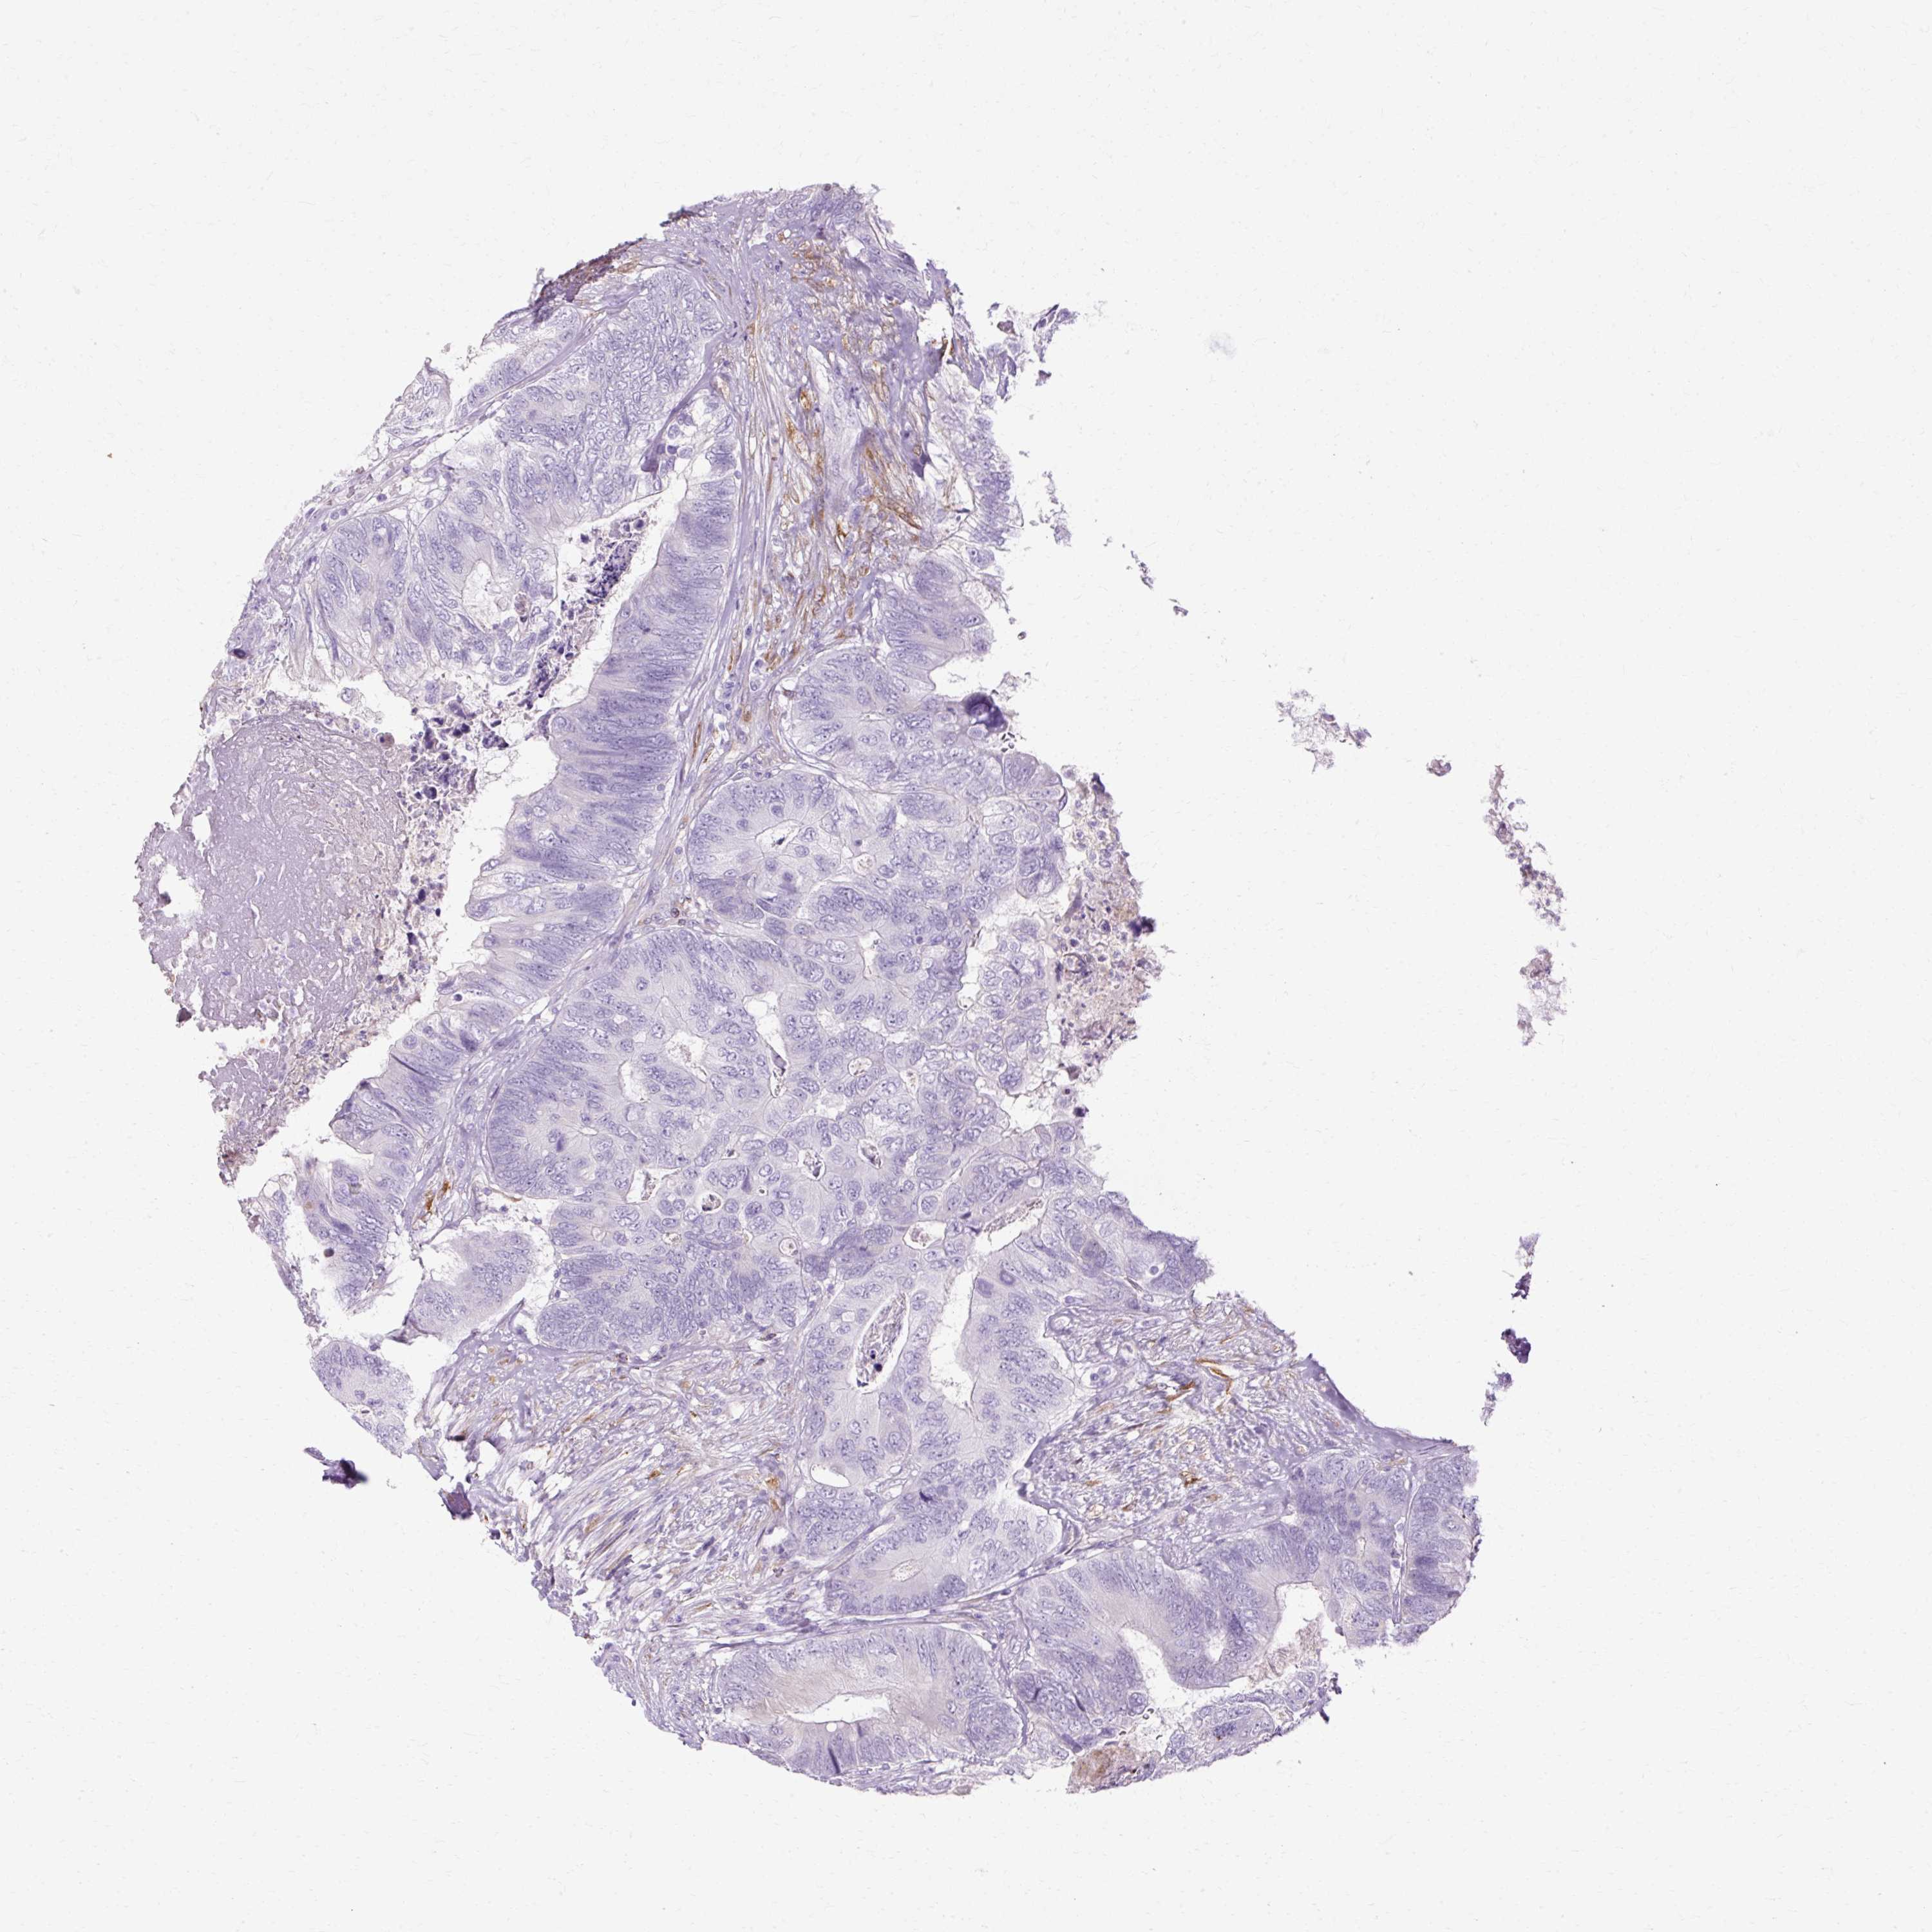

Colorectal cancer

Rectum adenocarcinoma

HSD11B1 is not prognostic in Rectum Adenocarcinoma (TCGA)